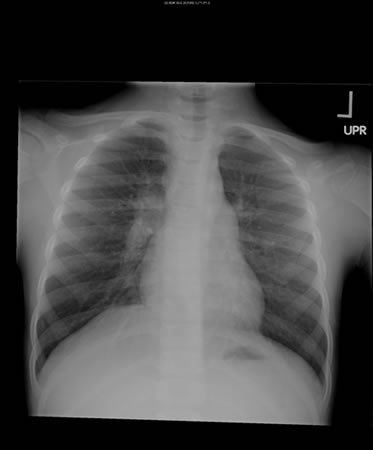

Em indivíduos imunocompetentes é quase sempre anormal. Apresenta-se tipicamente como opacidades fibronodulares nos lobos superiores com ou sem cavitação. O padrão atípico inclui opacidades nos lobos médio e inferior, linfadenopatia hilar ou paratraqueal e/ou derrame pleural.[Figure caption and citation for the preceding image starts]: Tuberculose pulmonar com cavitaçãoDo acervo pessoal de David Horne e do Dr. Masahiro Narita; usado com permissão [Citation ends].

[Figure caption and citation for the preceding image starts]: Opacidades no lobo inferior direito em um paciente com tuberculose pulmonar e diabetesDo acervo pessoal de David Horne e do Masahiro Narita; usado com permissão [Citation ends].